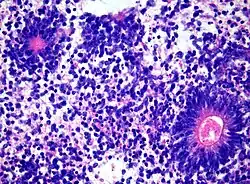

Medulloepithelioma, on the other hand, are tumors involving the constant cell division on the epithelium tissue where bundle of neuron endings are located.[1] Such tissue will differentiate into a similar form as the embryonic neural tube, also known as the starting structure of the central nervous system.[1][2][3] Medulloepitheliomas also present a pattern known as rosettes, characterized by the arrangement of a bundle of cells into circular shapes and around a center or a neuropil.[1] Ependymoblastoma also present rosettes as well as a higher density of cells.[1][3] It involves the process of differentiation into ependymal cells.[2][3]